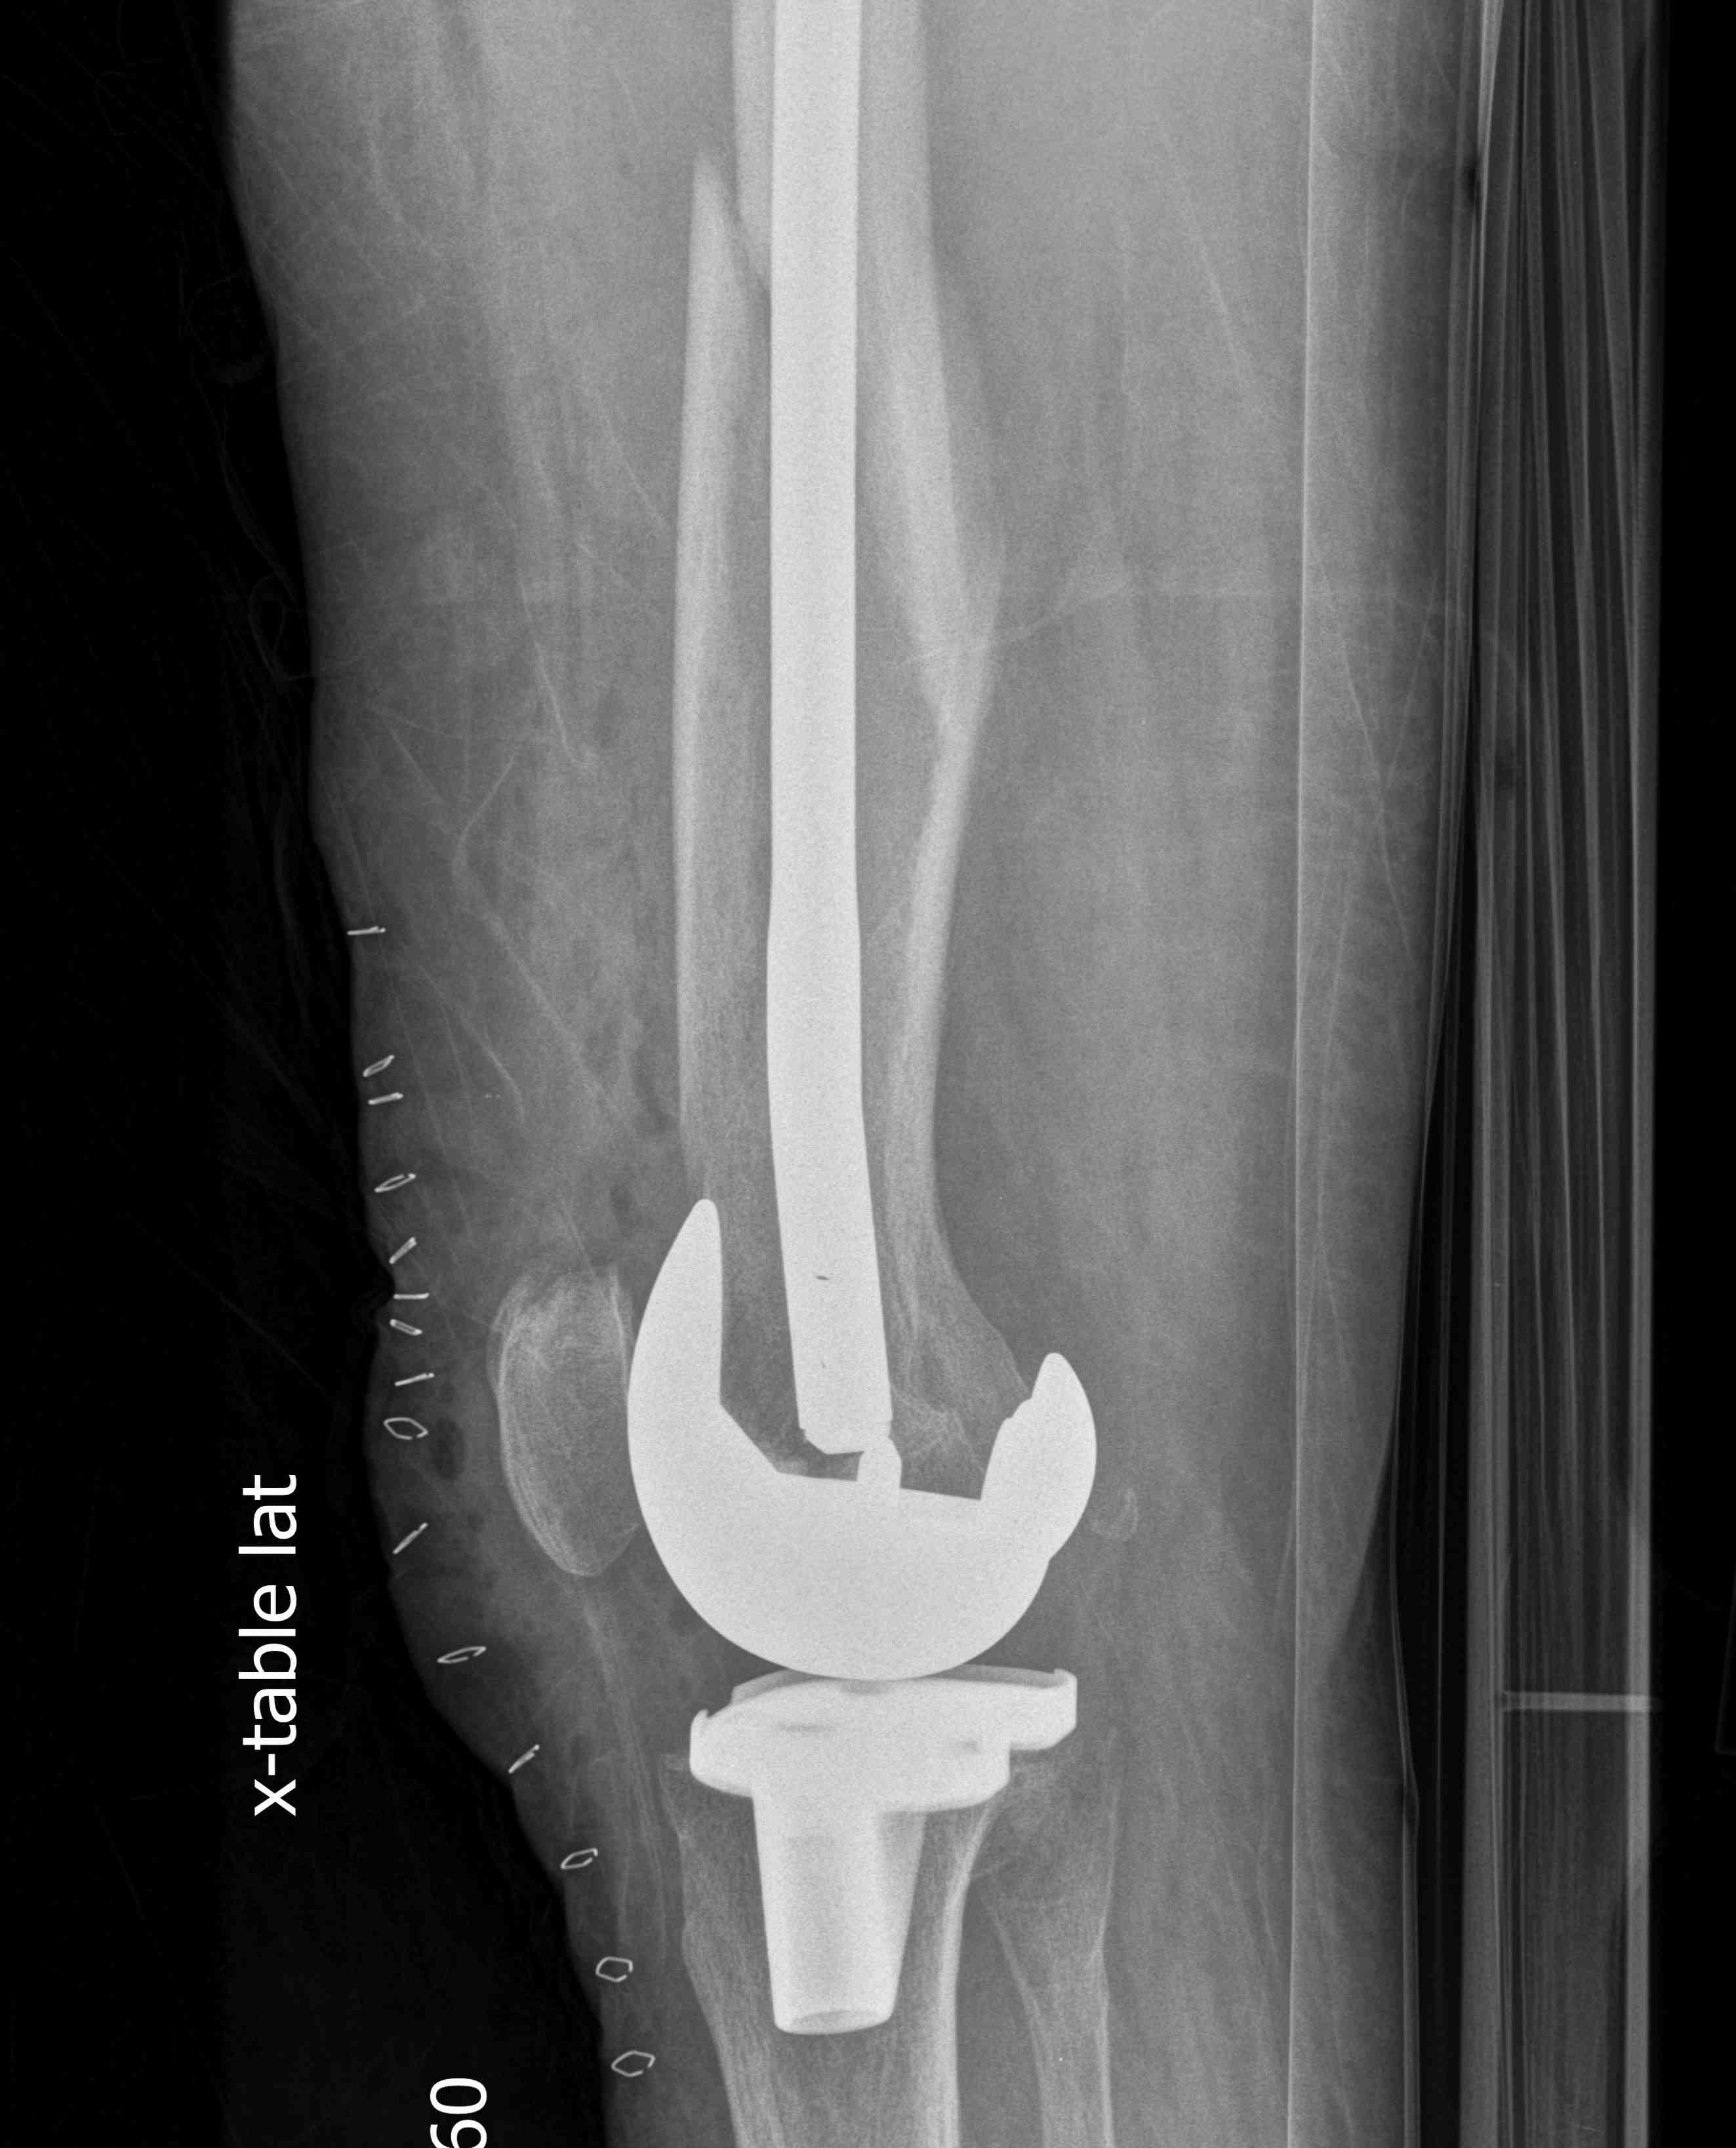

4.  Revision TKR

Indications

- very distal fracture

- insufficient bone stock

- loose prosthesis

Components

- stemmed, constrained implant

- tumour prosthesis

Case 1

Periprosthetic TKR Tibial Fracture 1Periprosthetic TKR Tibial Fracture 2Periprosthetic TKR Tibial Fracture 3Periprosthetic TKR Tibial Fracture 4

TKR Periprosthetic Fracture APTKR Periprosthetic Fracture LateralTKR Periprosthetic Fracture Revision APTKR Periprosthetic Fracture Revision Lateral